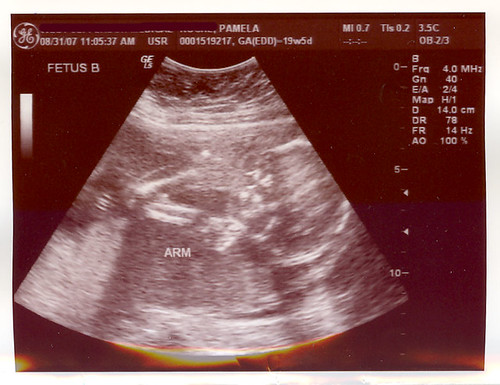

B: